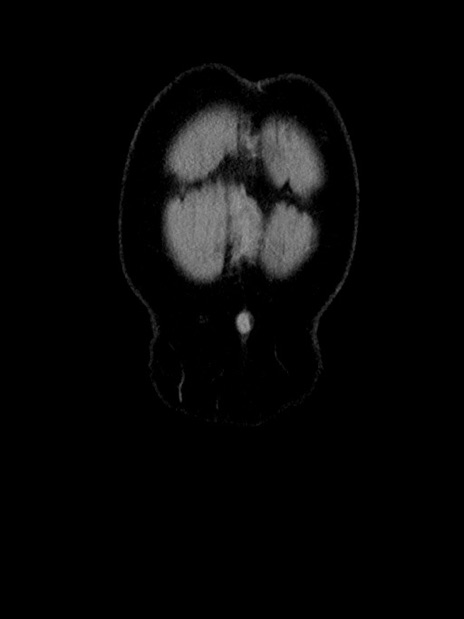

症例35(冠状断像)